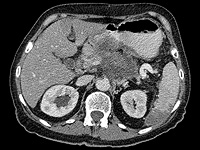

Wikipedia.org. Фото: Hellerhoff